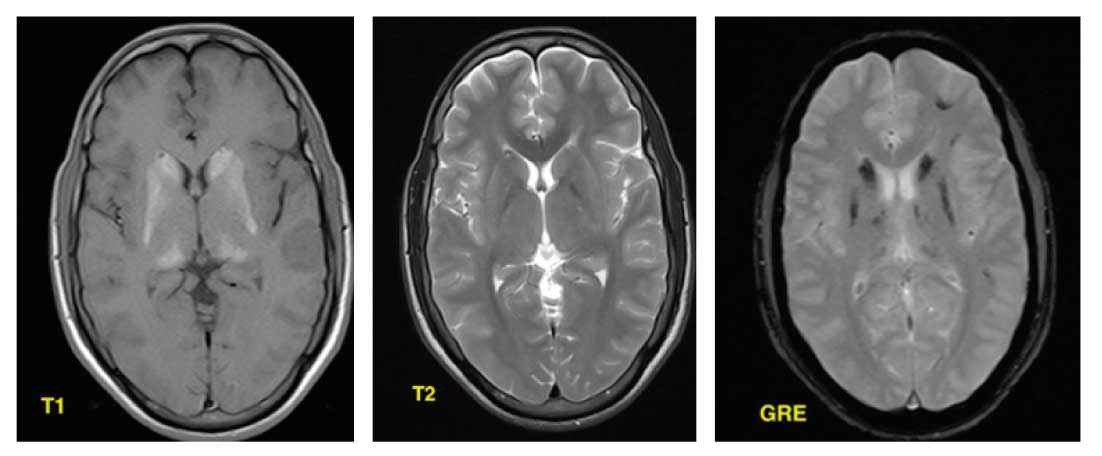

RM (Ressonância Magnética)

- T1 = áreas calcificadas tem hiperssinal (contrário das expectativas), atribuído ao efeito diamagnético do cálcio, das superfícies de seus cristais.

- T2 = baixo a isosinal, dependendo da diferença de composição dos depósitos de cálcio, como zinco, manganês, ferro ou magnésio.

- Altos sinais podem ser encontrados nos núcleos da base, substância branca e cápsula interna se não tiver calcificação, podendo corresponder ao lento processo inflamatório ou metabólico.

- T2* / SWI = marcado hiposinal.

- SWI é a sequência de maior sensibilidade para calcificações / produtos de degradação do sangue e ferro.